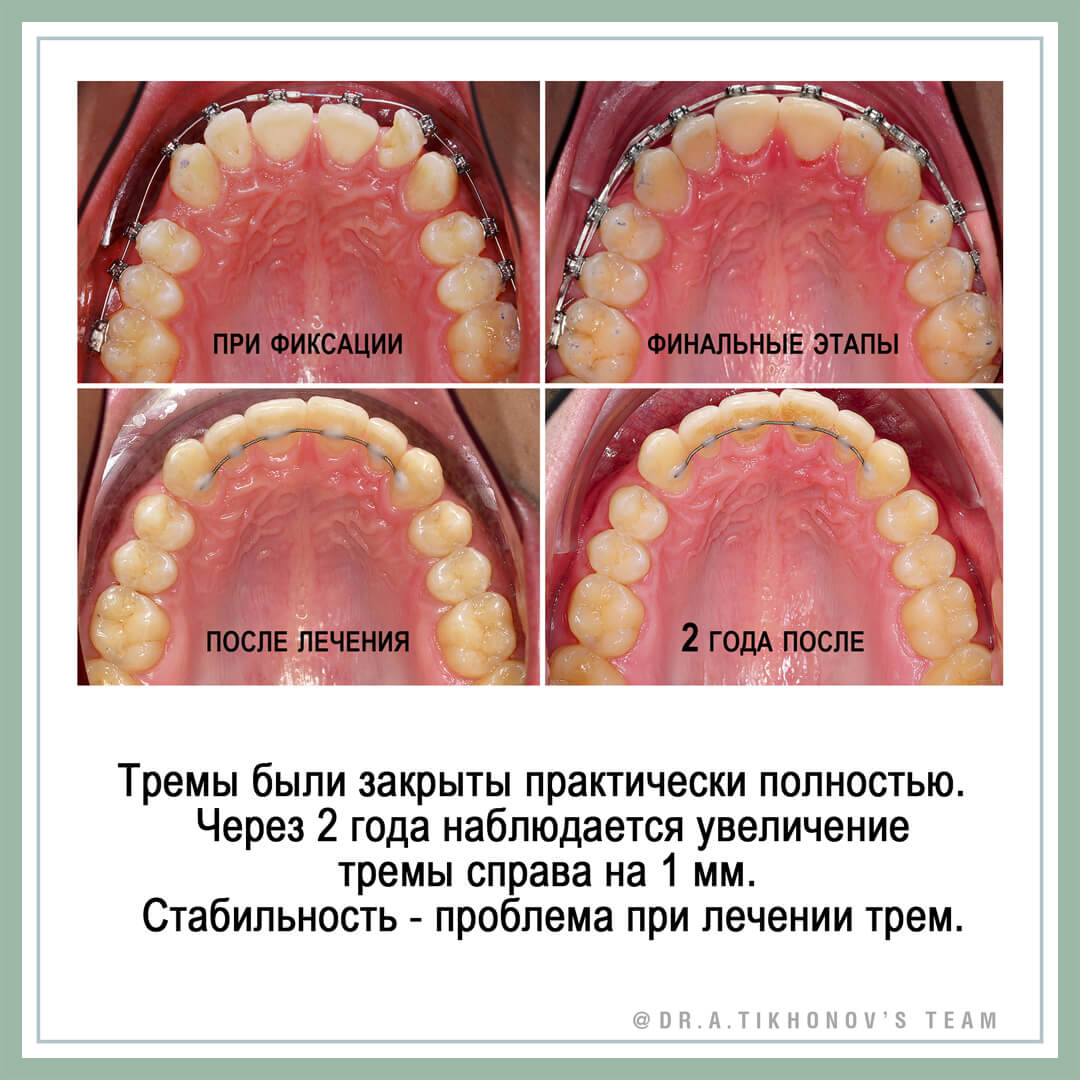

Закрыть все с уплощением зубных рядов. На слайдах такой пример (доктор Анна Мартиросян, клиника «Полный порядок»). Подходит, если зубы нормального размера, есть протрузия. Или тремы небольшие, и пациент отказывается от реставрации зубов. Закрываем цепочкой, начиная чаще с 1825. Сначала собираем передние, потом на рабочей дуге уже закрываем то, что за клыками. Внимание к языку (миогимнастика, шипы). Ретейнеры надолго (верх и низ), лучше прямоугольные. Предупредить, что тремы за клыками могут появиться снова.